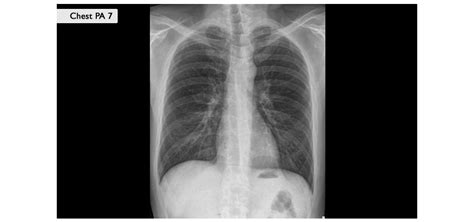

Pljučnica

Pljučnica je bolezen spodnjih dihal, torej bolezen pljuč, pri kateri se majhni zračni mešički vnamejo in napolnijo s tekočino ali gnojem. Pljučnice segajo od blagih pa do življenjsko ogrožajočih vnetij. Povzročajo jih bakterije in virusi, redkeje glive. Pri bakterijski pljučnici, pri kateri se pojavi tudi produktiven kašelj, je veliko izmečka. Telesna temperatura je lahko visoka, lahko pa tudi normalna, pri starejših in imunsko oslabelih osebah celo znižana. Oboleli pogosto navajajo simptome, kot so glavobol, bolečine v mišicah in prsih, hitrejše ali težko dihanje. Virusna pljučnica praviloma poteka blažje od bakterijske. Zanjo so značilni suh kašelj, glavobol, bolečine v mišicah in zvišana telesna temperatura. Pri blažjih oblikah so simptomi podobni kot pri prehladu ali gripi. Najbolj ogroženi so otroci, mlajši od 2 let, in starejši, zato hitreje potrebujejo zdravniško pomoč.